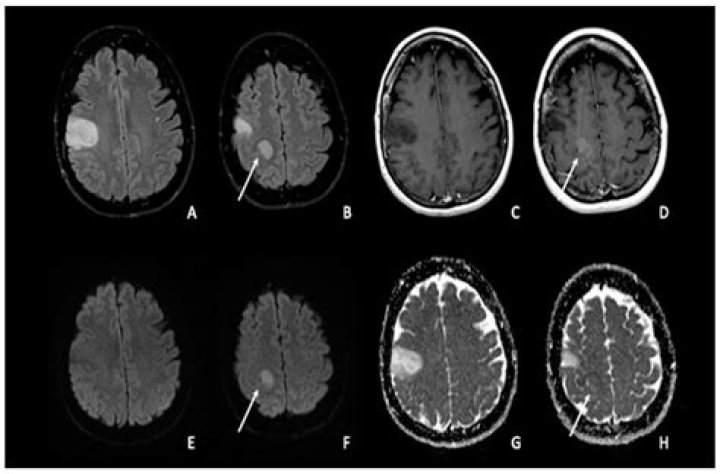

When brain tissue dies due to a reaction to radiotherapy it is called brain radionecrosis. Brain radionecrosis can cause damage to the patient's ability function. What this looks like depends where the radionecrosis has happened in the brain and it can impact on a patient's quality of life.

Postirradiation cerebral necrosis, the most direct effect of CNS irradiation, is thought to result from direct effects of radiation on the replicating glial cell compartments and the capillary endothelial cells.

What is Radiation Necrosis?